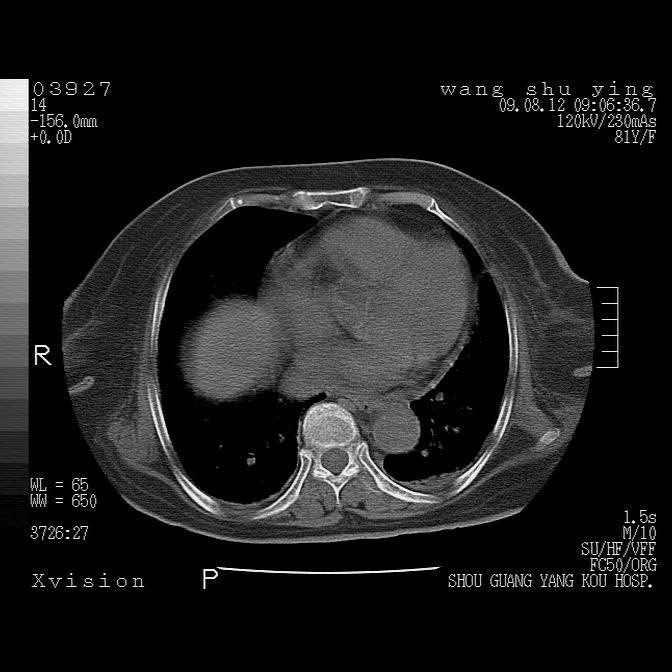

以下是引用帅河马在2009-8-12 12:59:00的发言:[br]两肺感染性病变伴双侧胸膜肥厚。[br]左侧甲状腺腺瘤不除外。[br]腹水+心包积液。[br][br][本贴已被 帅河马 于 2009-8-12 13:14:32 修改过]

以下是引用sdzyy在2009-8-12 18:17:00的发言:[br]两肺感染性病变伴双侧胸膜肥厚。[br]左侧甲状腺腺瘤不除外。[br]腹水+心包积液。[br]支持

以下是引用随光逐影在2009-8-12 19:42:00的发言:[br]1)两肺感染性病变伴双侧胸膜肥厚。2)不排除左侧甲状腺腺瘤。3)肝脏占位性病变;建议行进一步检查。